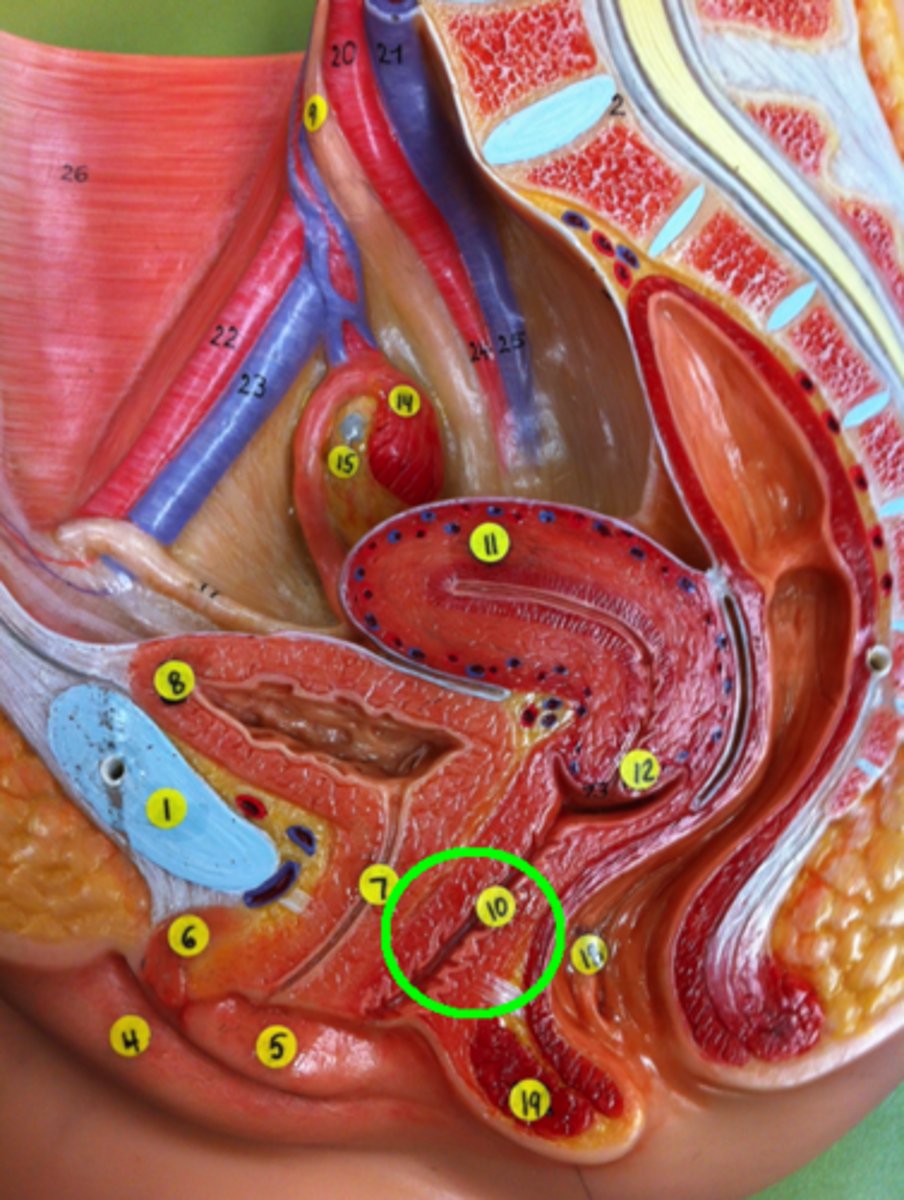

Urethra